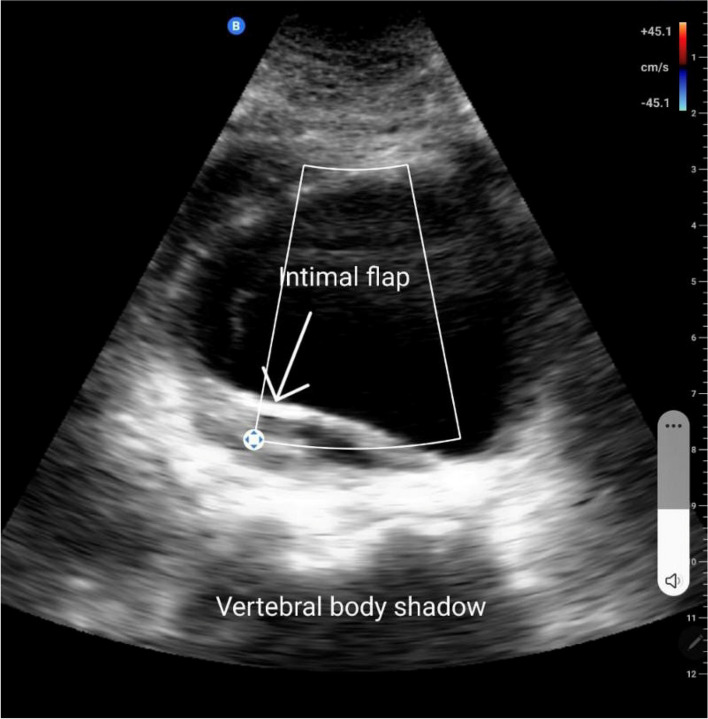

Four minutes later, he was arrested again, another 1 CPR cycle with adrenaline was done and the patient reverted again. Post-CPR electrocardiogram again demonstrated normal sinus rhythm without acute ST changes and the results of venous blood gas on the ventilator were PH = 7.295/pCO2 = 23.9 mmHg/cHCO3 = 11.4 mEq/L/ctCO2 = 12.1 mmol/L/BE (base excess) = − 13/pO2 = 138 mmHg/SO2 = 98%. During that, we noticed that his lower limbs were paler and colder than his upper limbs, thus carotid and femoral pulses were examined, and the examination showed a diminished femoral pulse when compared to the carotid pulse. Point of care ultrasound was done using the “Butterfly IQ ultrasound probe,” which is a portable pocket-sized probe that can be easily connected to a phone or a tablet (image shown in Fig. 1), and found a dilated abdominal aorta, around 8 cm, with an intimal flap. Despite starting a massive blood transfusion and giving 1 g of tranexamic acid, the vascular surgery team was not available until about one hour later, while they evaluated the patient in ED, his condition was extremely unstable. During that, laboratory results were out, and hemoglobin level dropped from 12.9 g/dL to 10.2 g/dL within a day, PO4 = 5 mg/dl, troponin = 64 ng/L. The patient was arrested again, and 8 cycles of CPR were done with adrenaline 1 mg given 4 times, the patient had pulseless electrical activity during the whole resuscitation process. Unfortunately, the patient died despite all these efforts.

Fig. 1.

A screenshot taken from the tablet connecting to the butterfly IQ probe showing about 5 cm aortic aneurism at the level of mid-aorta taken in transverse view with a large intimal flap